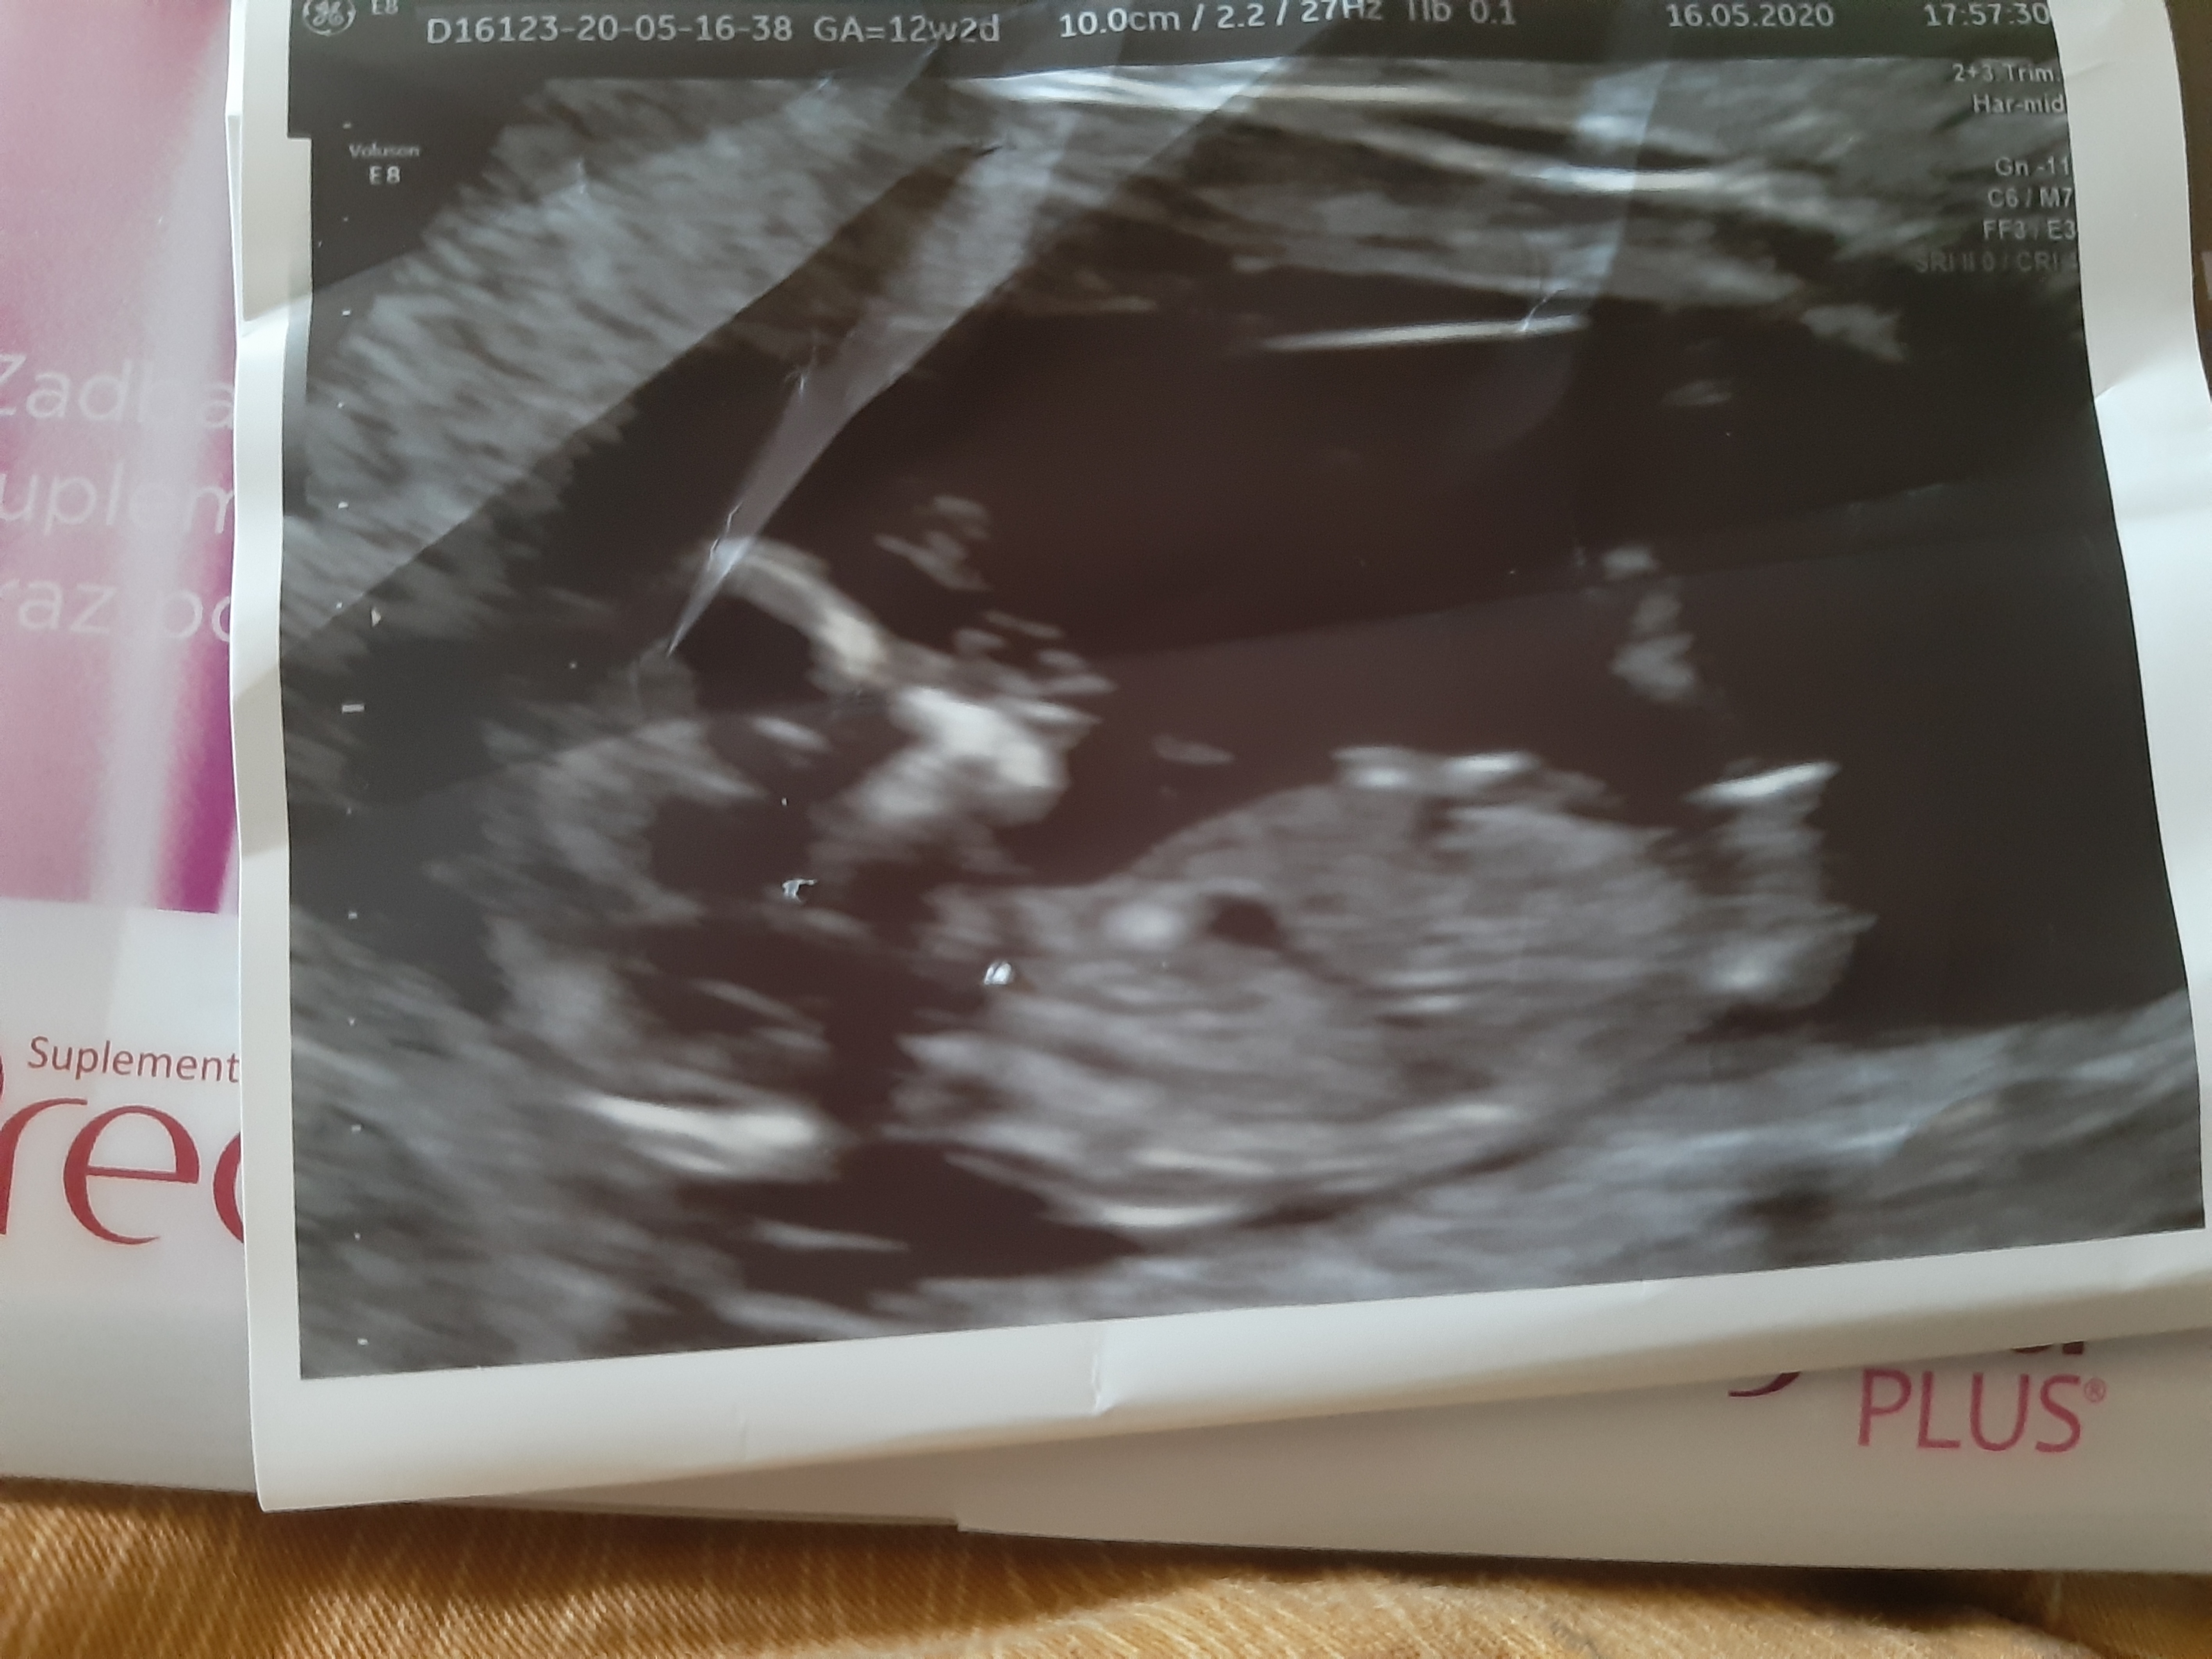

Super gratuluję , a masz jakieś zdjęcie z USG ,mogłabyś wrzucić tak dla porównania tylko 😉

Jasne tylko córka trochę wygniotla .... :) ( oglądała dzidziusia 😉

Załączniki